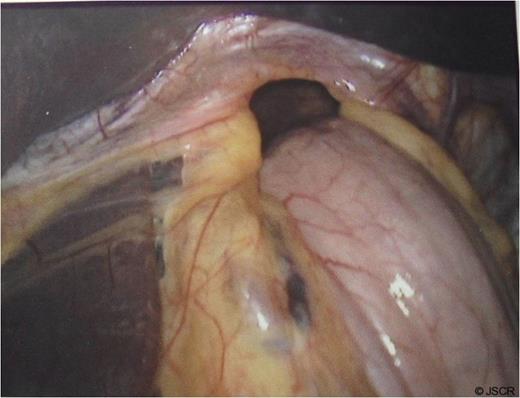

At operation, a large hiatal defect of 5cm and a moderate size sac was found (Fig 1) that was mobilised and adhesions divided to obtain 3cm of oesophageal length in the abdomen. Following division of the upper short gastric vessels, a posterior hiatal repair with seven interrupted ethibond stitches and a loose 360 degree full wrap with the fundus of the stomach with three interrupted ethibond stitches were performed. Wrap was further fixed to the diaphragm and right crus with another three ethibond stitches (Fig. 2).